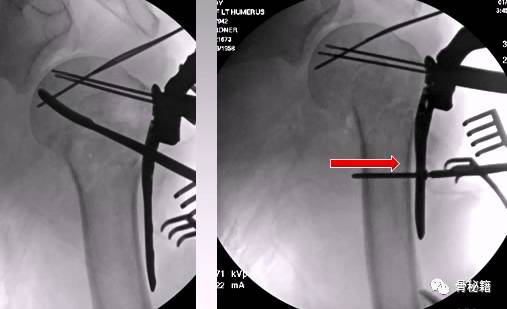

1、克氏针摇杆技术

正位的翘拨复位

腋位的翘拨复位